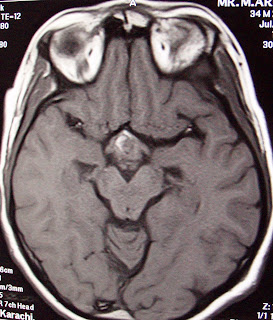

F.up images after one year showing complete resolution of

craniopharyngioma, clinically patient has normal vision and has no defecits.